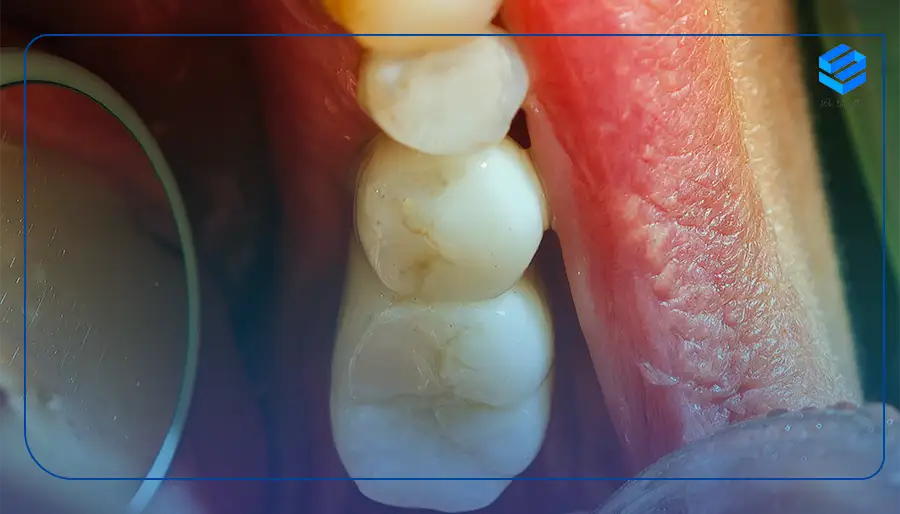

ایمپلنت دندان معمولا در سه بخش طراحی می شود. این سه بخش شامل پیچ ایمپلنت، اباتمنت و پروتز (ترمیم دندان) می شود. اباتمنت به پیچ ایمپلنت وصل می شود و پروتز می تواند شامل تاج یا بریج باشد.

در میان اجزای ایمپلنت دندان، پیچ ایمپلنت از طریق عمل جراحی کوتاه و با عمل کامپیوتری در استخوان فک قرار می گیرد. این بخش، ظاهری شبیه ریشه دندان طبیعی دارد و در قطر های مختلفی در دسترس است. اباتمند ها جهت پشتیبانی از پروتز مورد استفاده قرار می گیرند و تفاوت عمده ای با آن دارند، چرا که ایمپلنت دندان مصنوعی ضمائم به خصوصی را در سطح فیتینگ دارد. این اجزا به اباتمنت وصل می شوند و بعد از آن پروتز بر روی میله سوار می شود.